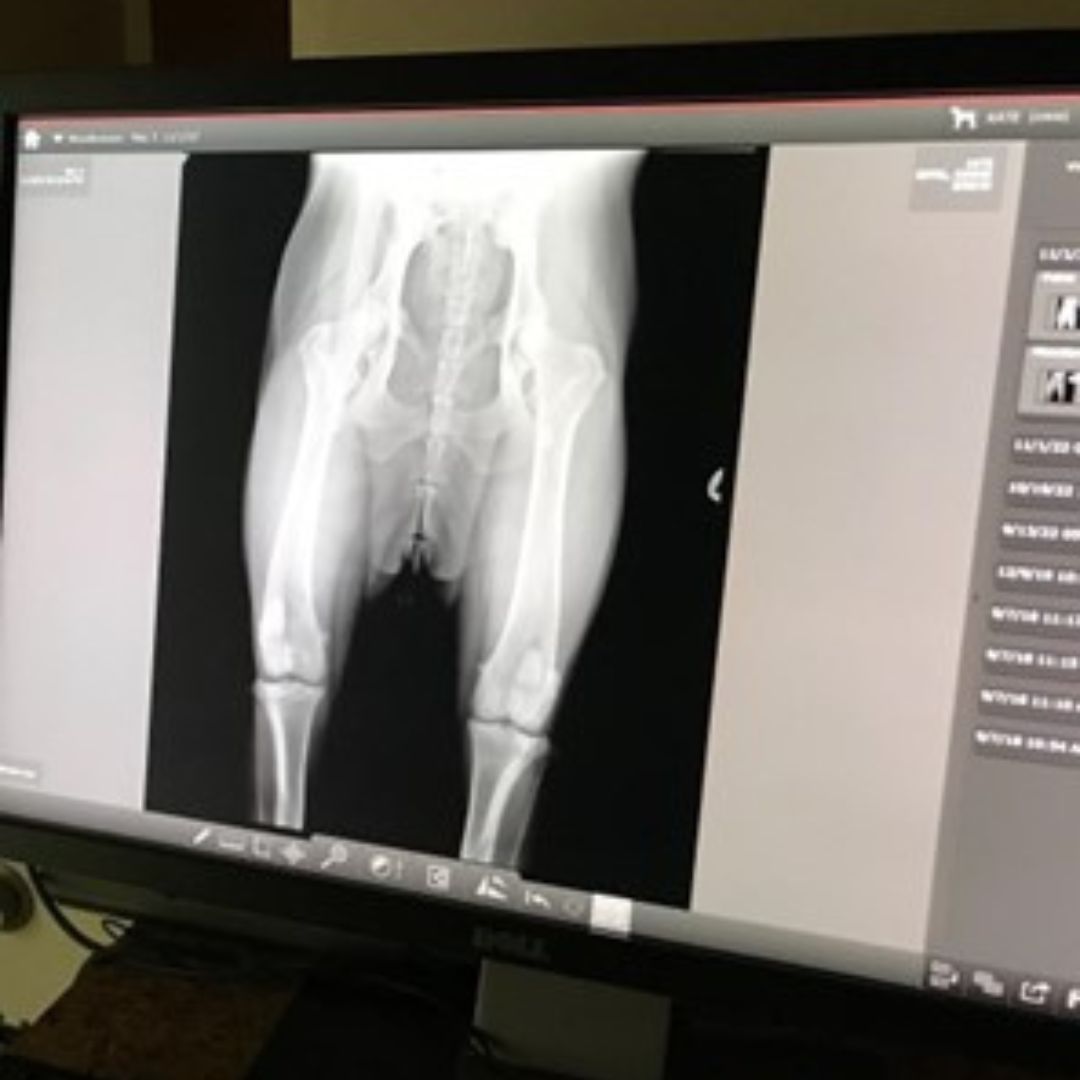

At Magic Valley Veterinary Hospital, digital radiology is a tool we commonly implement to assess injuries, detect internal conditions, and provide precise diagnoses for pets. This advanced imaging technology allows us to capture high-quality X-ray images quickly and efficiently, ensuring timely and effective treatment.

- Enhanced Image Quality: High-resolution images improve accuracy in detecting fractures, organ abnormalities, and other health issues.